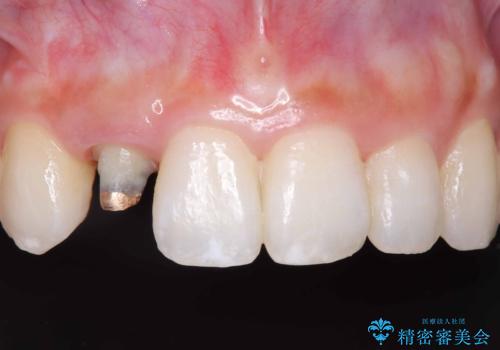

被せ物と歯の境の位置が歯肉の上に設定されており、それによって審美障害が起きていました。

歯と被せ物の境を歯肉縁下0.5㎜に設定して形成を行いオールセラミッククラウン(スペシャル)で治療を行いました。